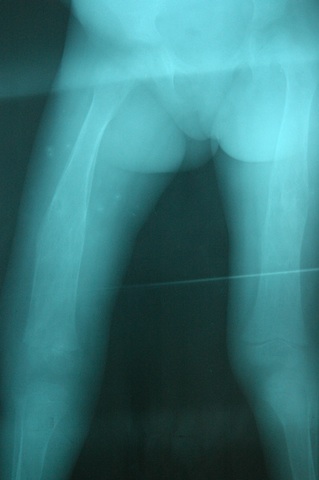

Medical 8-05 to 6-06

Image Date: 6/1/06 7:27:04 AM PDT